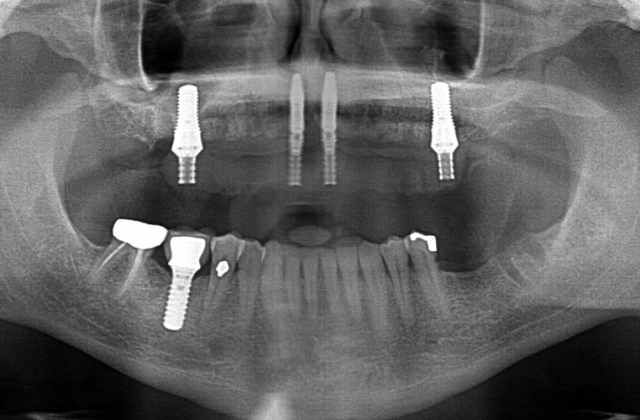

It is incredibly important for us to properly treatment plan these cases to mitigate potential risk and complications. Certainly the greatest risk is not providing enough prosthetic space. It is paramount the surgical team create enough vertical height from the implant level to the incisal edge of the prosthesis.

There has to be enough vertical height to stack components: abutments, Ti bar, the acrylic wrap and denture teeth. It is commonly reported in the literature that a minimum vertical height requirement is 15 to 16 mm from the fixture to the incisal edge.

It is possible to restore a case with only 13 mm, but careful coordination is required with the lab, and certain patient anatomic and occlusal relationships are required.

If there is insufficient space, the patient will suffer from a failure of the prosthesis (displaced teeth, fractured provisional, or – rarely – a fractured bar or abutments) or potentially an un-esthetic outcome with the plane of occlusion in the wrong position in the vertical dimension of the face.

5. When the anatomy allows, plan the case for straight abutments, which will save you a minimum of 2.5 mm with any implant system on the market. It’s not always possible, but when I can, I routinely use straight abutments, especially in the anterior.

6. Use a soft-tissue implant in the posterior and eliminate the use of an abutment. Take the final bar straight to the implant. I frequently use this option when there is enough bone after the reduction and the anatomy allows the use of a vertically placed implant. I like using a wide-neck, wide-body implant in the first molar sites; the final bar will go straight to the implant connection. Additionally, the screws are big and beefy and are torqued to 35N/Cm. The A-P spread is very favorable, there is a huge surface area with these implants with higher bone-implant contact, and second molar occlusion is achievable. Posterior space is always at a premium with the arc of closure, and eliminating a posterior abutment will save at least 3.5 mm of space over an angled abutment.